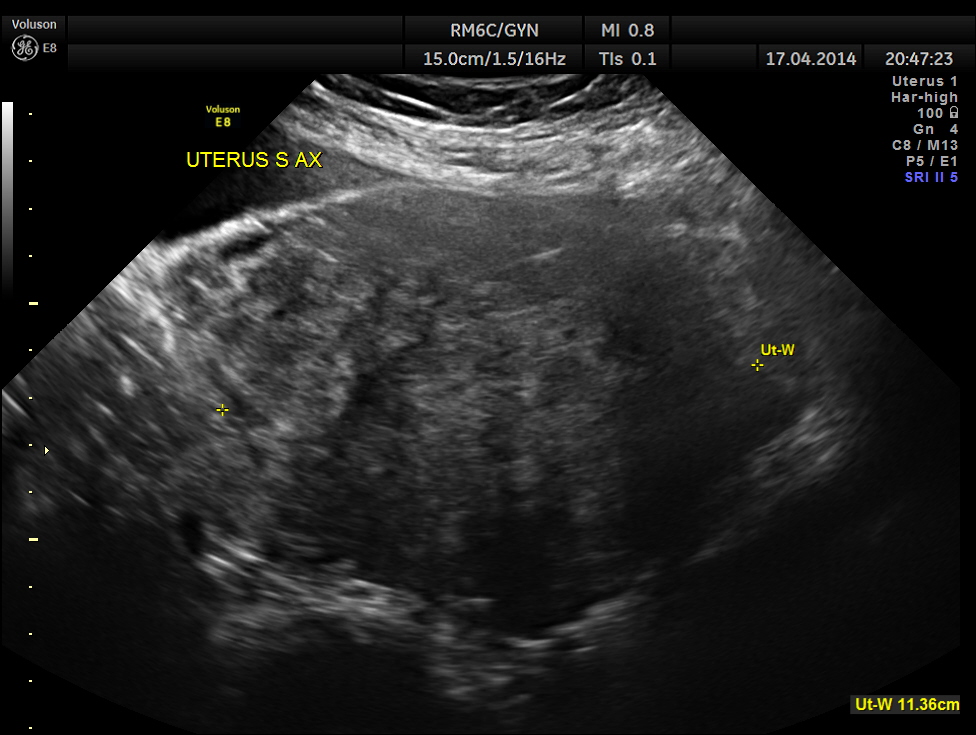

Uterus was massively enlarged and showed a large fibroid . Uterine texture also showed features of adenomyosis and endometrial thickening.

The ultrasound gave us a few inconclusive findings . Uterus was massively enlarged ; a large fibroid was seen ; adenomyosis was seen ; endometrium was thickened ; two large mass lesions were seen in the right upper quadrant and right lumbar region . But it was difficult to ascertain the origin of these extra uterine masses .